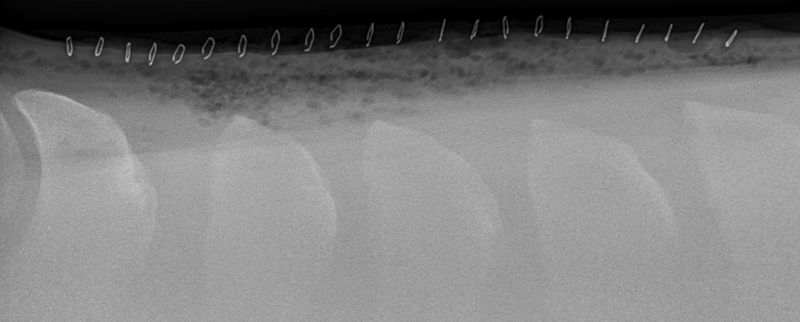

HORSE “A” PRE-OP X-RAY

Shows Impingement of the Dorsal Spinous Processes

HORSE “A” IMMEDIATELY POST-OP X-RAY

Shows Corrected Dorsal Spinous Processes After Bone Reduction Procedure Performed by Dr. Cliff Honnas

HORSE “A” 3-YEAR POST-OP X-RAY

Shows Lasting Results from Bone Reduction Procedure Performed by Dr. Cliff Honnas

The second surgical option considered for Kissing Spines patients is a bone reduction procedure. Dr. Honnas is recognized as one of the foremost experts in the country at performing this procedure and garnering impressive long-term results for Kissing Spines patients.

“The bone reduction surgery that I do removes bone at each impinging space, then recreates a space between those adjacent bones,” says Dr. Honnas of the surgical method. While some practitioners prefer to perform this procedure on the standing horse, Dr. Honnas’ preference is to operate on these cases under general anesthesia laying left-side down. A primary reason for this preference is that the position of the horse alleviates the weight of the gut, so it no longer pulls the dorsal spinous processes closer together. “I pull them to the edge of the table, make an incision right on the midline and cut through the skin. I then cut through the dorsal spinous ligament (the ligament over the top of the backbone) and cut away the muscles on either side of the dorsal spinous processes,” he explains of his technique technique. “There’s no way to take away that bone without removing the ligament. Next, I cut the interspinous ligament that's between each dorsal spinous process, then using my right hand with a pair of bone-cutting forceps, I cut away on the bone that's behind each impinging space. I cut a piece, and I feel with my left index finger. I’m removing the interspinous ligament and the front edge of the backbone at each impending space.” It’s a gradual process where Dr. Honnas cuts, feels, cuts, feels and so on, being sure to trim up any rough edges on the bone as he goes. “When finished, I can get my index finger between the bones all the way down to where the space opens up again. Usually, they’re going to be pretty tight for about 1.5 to 2 inches, then open up naturally below that,” he says of the anatomy of the back following surgery.

The number of bone reduction procedures that Dr. Honnas performs has risen dramatically in conjunction with improved diagnostics and veterinary familiarity of Kissing Spines. Performing roughly 145 of these procedures in the last year on horses from every corner of the country, Dr. Honnas and his team are known for their exceptional track record. “I tell my clients, if this is a confirmed case of Kissing Spines, then this surgery will fix your horse,” he says with confidence. He and his team have achieved a 90 percent success rate, allowing patients to go on to live and compete free of the pain they once endured as a result of Kissing Spines.